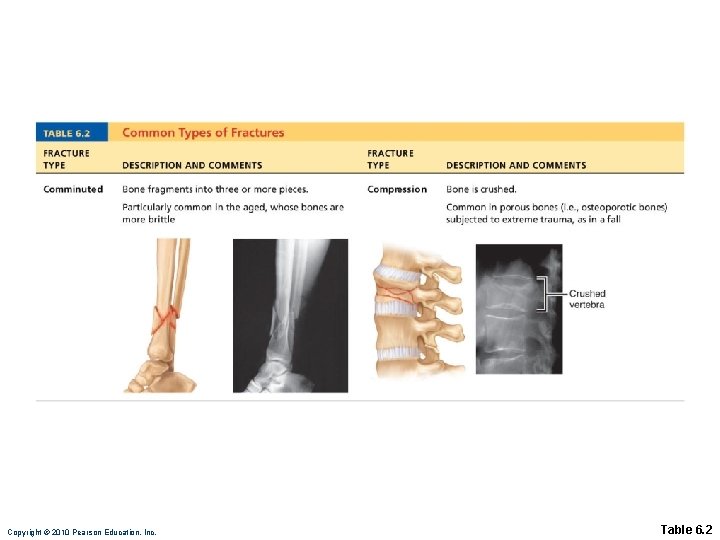

Common Types of Fractures • All fractures can be described in terms of • Location • External appearance • Nature of the break Copyright © 2010 Pearson Education, Inc.

Copyright © 2010 Pearson Education, Inc. Table 6. 2